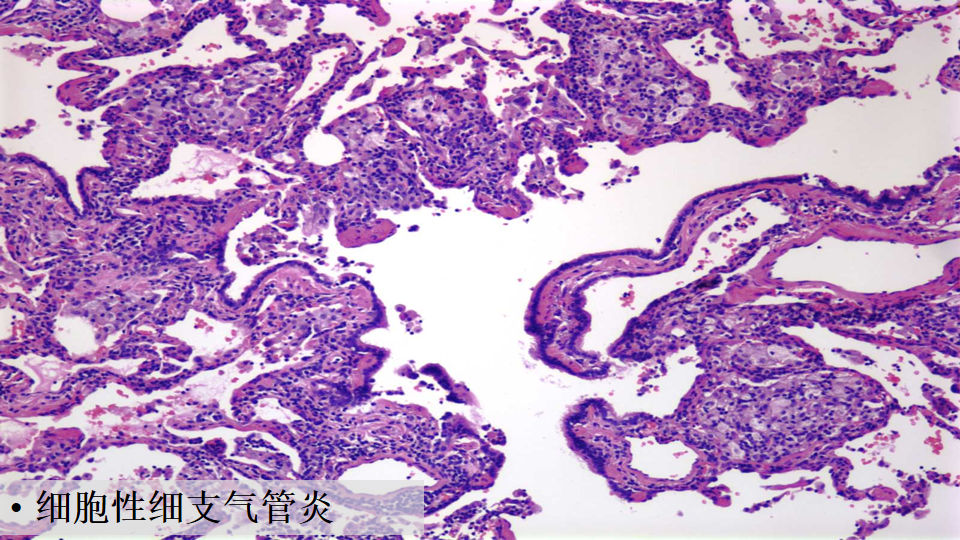

肺组织病理中,非纤维化型HP包括细胞性间质性肺炎(可见细支气管中心性分布,细胞性NSIP型,以淋巴细胞为著)、细胞性细支气管炎、未形成非坏死性肉芽肿(与结节病的肉芽肿呈显著差别)。纤维化型HP包括慢性纤维化性间质性肺炎(结构扭曲、成纤维细胞灶±胸膜下蜂窝肺纤维化性NSIP型)、气道中心性纤维化。

比如细胞性细支气管炎(下图左),可以看到很多淋巴细胞浸润;还有非坏死性肉芽肿炎(下图中),肉芽肿的边界并不清楚,有一些内上皮细胞和炎症浸润;细胞性慢性间质性肺炎——「NSIP样改变」(下图右)。